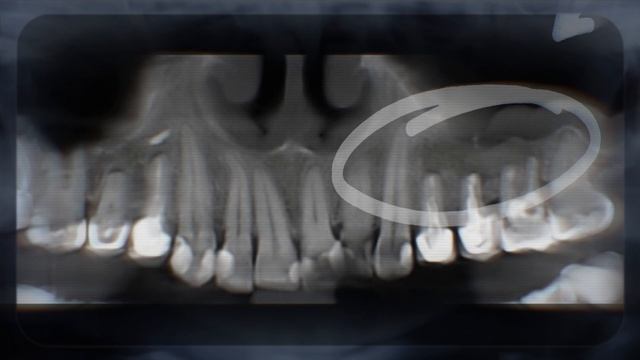

Пациентке сказали, что нужно удалить сразу три зуба из-за большой кисты. Но мы попробовали другой путь — сохранить их. Как проходило лечение, какие сложности возникли и почему через год пришлось выполнить повторную операцию. Посмотрите, чем всё закончилось и почему не всегда стоит спешить с удалением зубов. Подписывайтесь на наш канал, чтобы первыми узнавать о новых возможностях современной стоматологии! Ставьте лайк, если материал был для вас полезным! https://doktorkonnov.ru/ https://vk.com/dr.konnov.stav/ г. Ставрополь, ул. 50 лет ВЛКСМ, 33 тел.: +7 (8652) 56-86-03 Время работы: Будни с 9:00 до 20:00 Сб. с 9:00 до 16:00 Вс. с 9:00 до 14:00